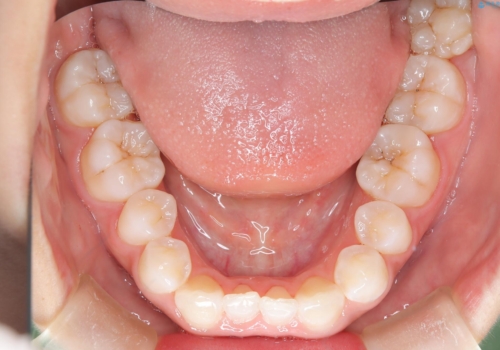

- 子供のころに矯正治療をされていたが、後戻りをしてしまったという20代女性の患者様です。上顎左右の2番が、咬合時に下顎の歯よりも内側に入っているクロスバイトという状態でした。奥歯の咬合関係は変えずに、マウスピース矯正にて前歯の並びを綺麗なアーチに仕上げました。再度後戻りしてしまうリスクを軽減させるために、リテーナー(保定装置)をお渡ししています。